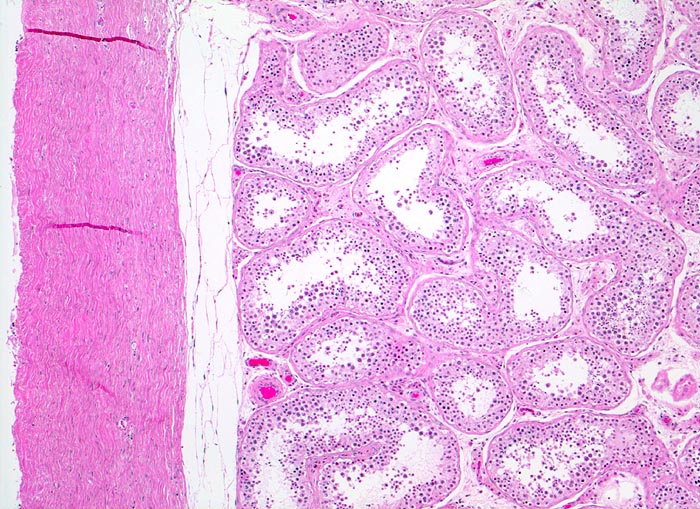

Makroskopisch imponieren Seminome als gut begrenzte weiche crèmefarbene Knoten oder diffuses Intiltrat. Mikroskopisch findet sich eine uniforme Population grosser Zellen mit prominentem zentralem Nukleolus, welche durch schmale Bindegewebssepten voneinander getrennte Nester bilden. Ein leukozytäres Entzündungsinfiltrat, synzytiotrophoblastäre Riesenzellen und Mikroverkalkungen können zusätzlich vorhanden sein. Gelegentlich induziert der Tumor eine ausgeprägte granulomatöse Entzündung. Dies kann zur Fehldiganose einer granulomatösen Orchitis führen.

Die Keimzellneoplasie in situ (atypische Keimzellen in Hodentubuli) ist die nicht invasive Vorläuferläsion fast aller Keimzelltumoren beim Erwachsenen (Keimzelltumoren Typ II). Diese kann fast immer in der Nachbarschaft eines invasiven Tumors nachgewiesen werden. Spezifische fortgeschrittenere Formen der Keimzellneoplasie in situ sind das intratubuläre Seminom und das intratubuläre Nicht-Seminom.

• Scharf begrenzter Tumorknoten mit eosinophilen Nekrosearealen.

• Unterschiedlich breite solide Tumorzellstränge aus monomorphen Zellen mit grossen hyperchromatischen Kernen und einem solitären zentralen prominenten Nukleolus. Reichlich helles Zytoplasma mit scharfen Zellgrenzen.

• Schmale bindegewebige Septen mit Kapillaren und lymphoplasmazellulärem Entzündungsinfiltrat.

• Tubuläre Atrophie des angrenzenden Hodenparenchyms. Einige Hodentubuli enthalten stark atypische pleomorphe Keimzellen (Keimzellneoplasie in situ).